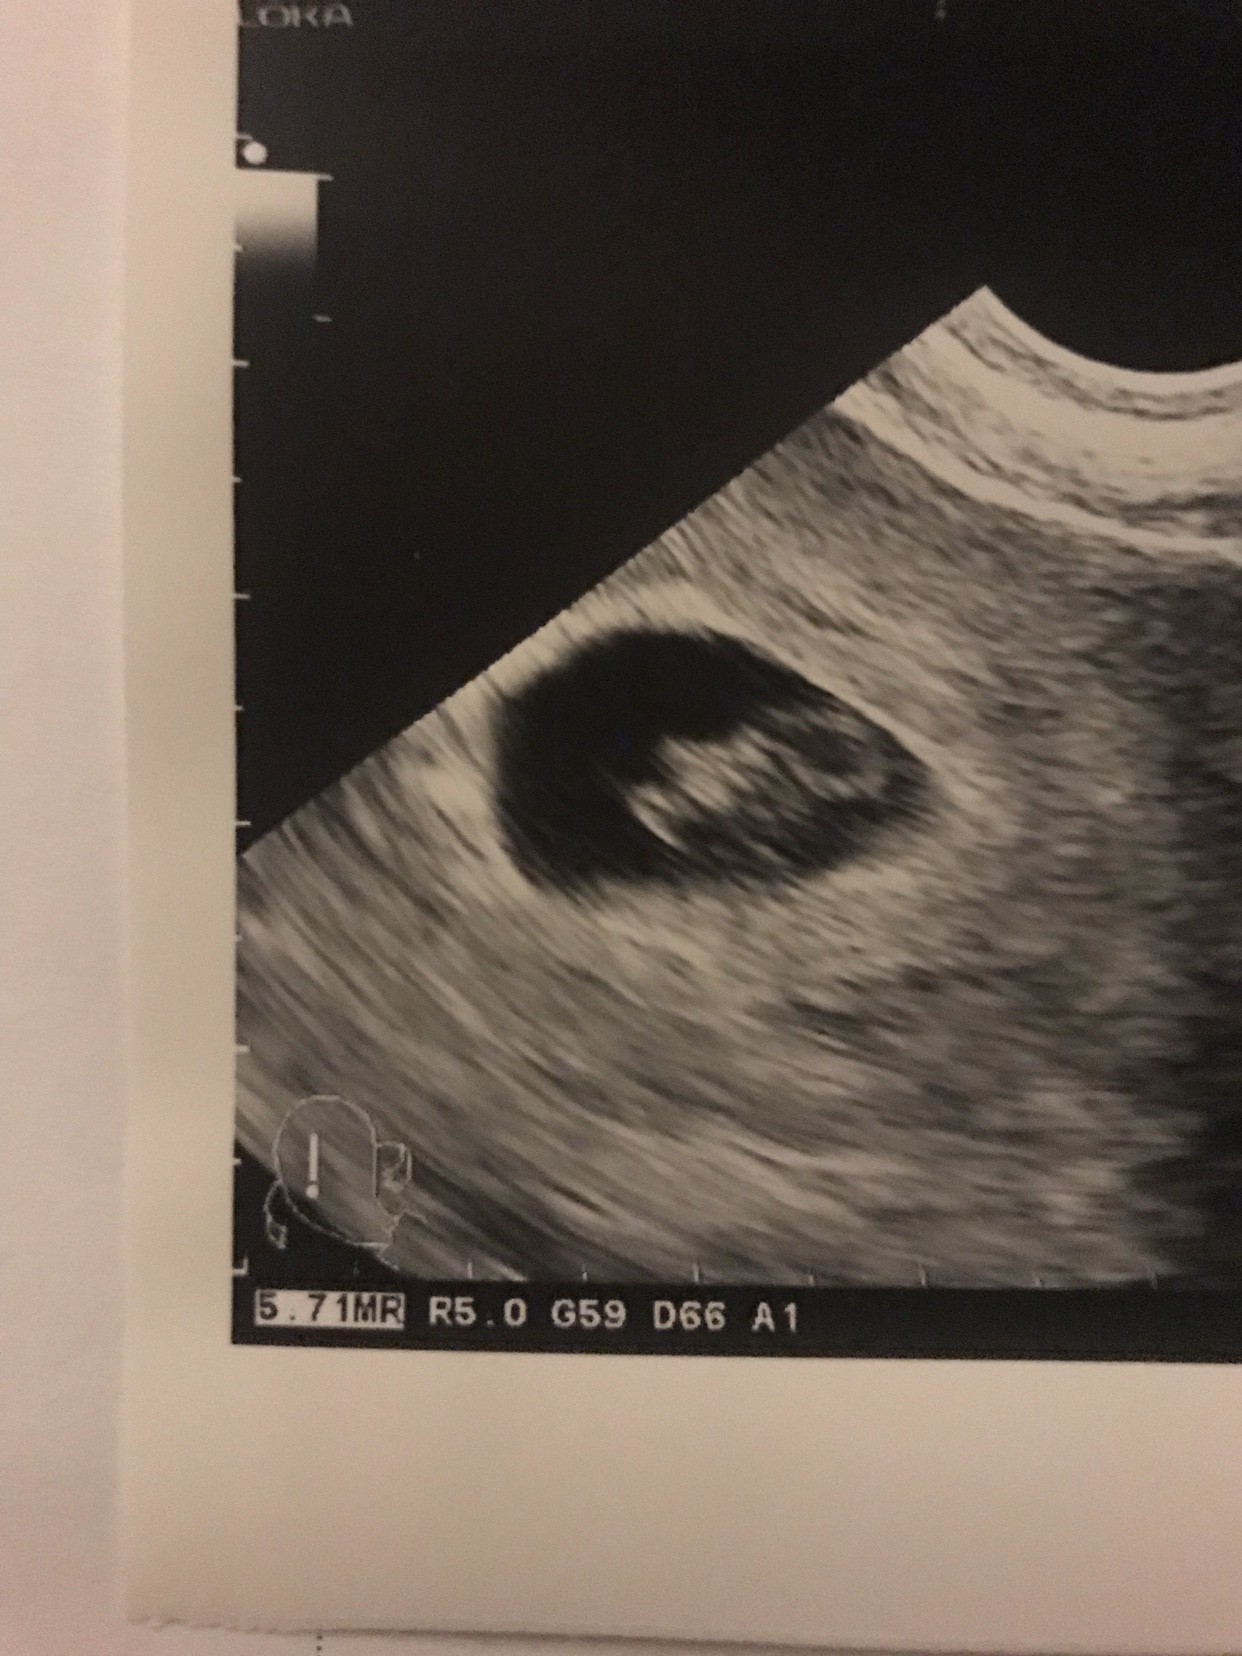

Jaka duża jużMoja kijanka kochana!![]()

PięknaZobacz załącznik 909225

Moja kijanka kochana! [emoji7][emoji7][emoji7]